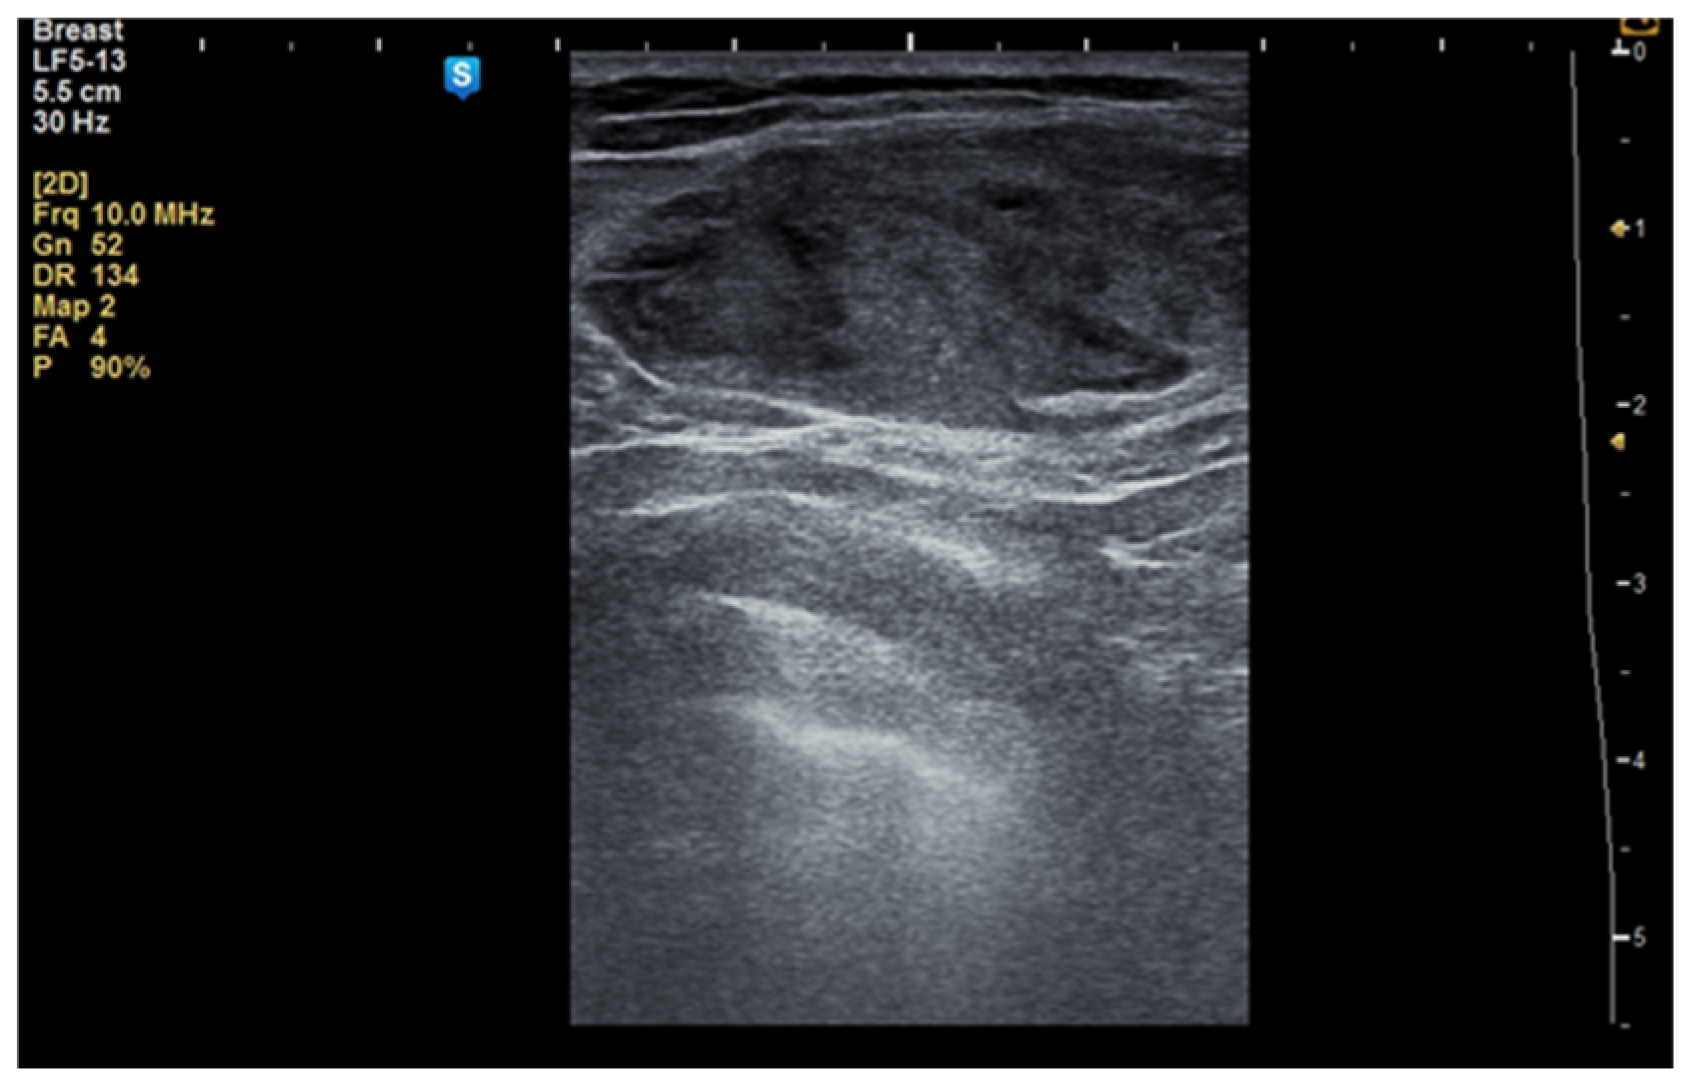

Although the literature identifies mammography as the primary diagnostic method for breast hamartomas, in our study, the diagnosis was established via ultrasound examination. This preference is due to the younger age of many patients, with only three being over 50 years old. On ultrasound, hamartomas typically appear as oval, well-circumscribed masses with heterogeneous hypoechoic or isoechoic echostructures and reduced or absent vascularity (Figure 1 and Figure 2). In our study, the concordance between ultrasound and histological size was 84.61%. Preoperative ultrasound diagnosis of hamartoma was established in only five patients, representing 38.46% of the cases.

Figure 1.

Ultrasound image of a 34-year-old woman with a right breast hamartoma of 65/35 mm, with heterogeneous hypoechoic structure, located in the upper inner quadrant.

Figure 2.

Ultrasound image of a 53-year-old woman with a right breast hamartoma with reduced vascularity, located in the lower inner quadrant.